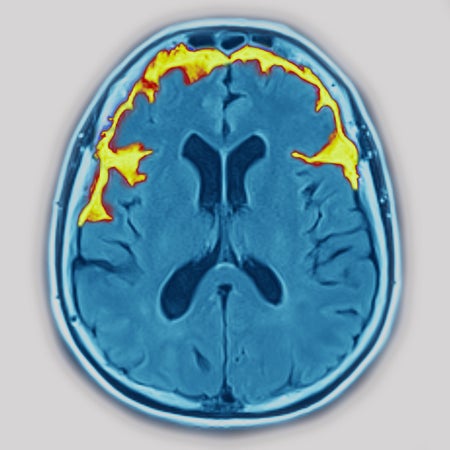

This Is Your Brain on Climate Change

Extreme heat caused by climate change can exacerbate a variety of neurological ailments, from Alzheimer’s disease to migraines to epilepsy, new research shows